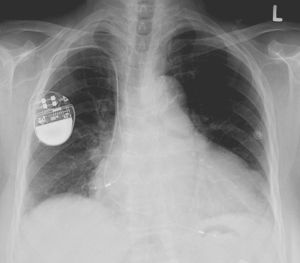

Pacemaker återkallas på grund av att de kan hackas Nästan en halv miljon pacemakers måste uppdateras Pacemaker återkallas på grund av att de kan hackas Foto: Lucier Monfilis / Wikipedia Den amerikanska myndigheten FDA (Food and Drug Administration) har beslutat att runt 465.000 pacemakers från tillverkaren Abbott måste återkallas för att installera en uppdatering rörande ett säkerhetsproblem. Det är ett antal av Abbots modeller som nu måste få sitt firmware uppdaterat men det ska vara en process som bara tar cirka 3 minuter enligt företaget. Det framgår inte exakt hur denna uppdatering går till men jag antar att det är något man måste fixa på sjukhus om man har en av de berörda modellerna. Säkerhetsuppdateringen kommer att innehålla: